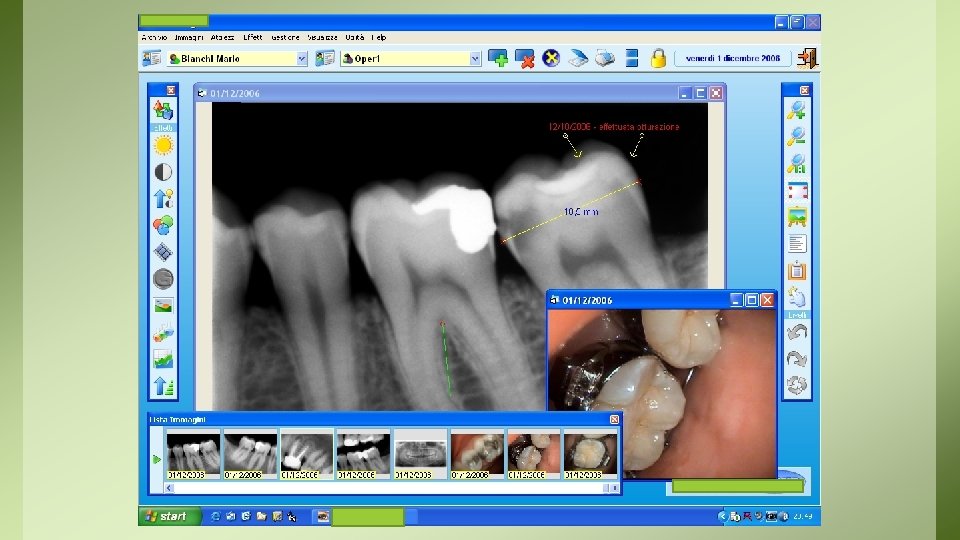

Documentazione Radiologica Sul tema della conservazione della documentazione di diagnostica per immagini, il D. M. del 14 febbraio 1997 (9)distingue: • a) documenti radiologici e di medicina nucleare, definiti come la “documentazione iconografica prodotta a seguito dell’indagine diagnostica utilizzata dal medico specialista nonché… quella prodotta nell’ambito delle attività radiodiagnostiche complementari all’esercizio clinico”; • b) resoconti radiologici e di medicina nucleare, cioè i “referti stilati dal medico specialista radiologo o medico nucleare”.

• La documentazione radiologica di cui al punto a) deve essere conservata (su pellicola radiografica, supporto cartaceo o elettronico) per un periodo NON inferiore ai 10 anni, ed essere resa disponibile e/o consegnata su richiesta al paziente o agli aventi diritto. – NOTA: per le CBTC deve essere assicurata adeguata archiviazione e conservazione del consenso informato per un periodo di almeno 5 anni e di tutte le immagini per non meno di 5 anni (come da raccomandazioni ministeriali del 2010) • La documentazione radiologica di cui al punto b) va invece conservata illimitatamente.

D. LGS. 187/2000: gli esami diagnostici di radiologia sono giustificati e attribuiti ai dentisti come attività complementare all’espletamento della propria branca specialistica solo come ausilio DIRETTO E IMPRESCINDIBILE alla prestazione clinica Ne deriva che non possono essere effettuati esami per conto di altri professionisti, né essere redatti o rilasciati referti radiologici configurandosi in tal caso come esercizio della professione di radiologo. Per lo stesso motivo non ha alcun presupposto la consegna in automatico della radiografie effettuate al paziente, poiché si configurerebbe come prestazione radiologica a se stante alla stregua del radiologo. Il professionista è comunque obbligato alla consegna, in originale o, meglio, in copia unitamente al resto della cartella clinica la paziente che ne facesse richiesta, previa firma di verbale di consegna.

REGISTRO ESAMI RADIOLOGICI • Ai sensi dell’art 12 del DL 187, è obbligatorio registrare tutti gli esami radiologici effettuati, quindi ogni singola lastra. • Il registro può essere cartaceo, in caso di radiografia digitale, il programma di radiologia deve consentire la stampa dell’elenco di radiografie effettuate.